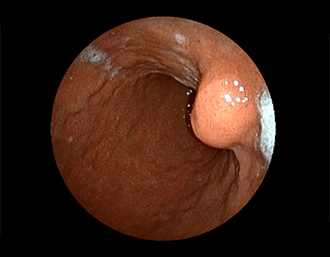

症例1:胃潰瘍(37才、男性)

①胃潰瘍(Stage A1)

健診:胃レントゲン検査で、胃角部ニッシェを指摘され当院受診。

胃角部小弯に、深くて大きな、大きさ約10mmの胃潰瘍(stage 1)があり、潰瘍底は一部白苔はみ出しを認める。エソメプラゾールマグネシウム水和物投薬で治療開始しました。